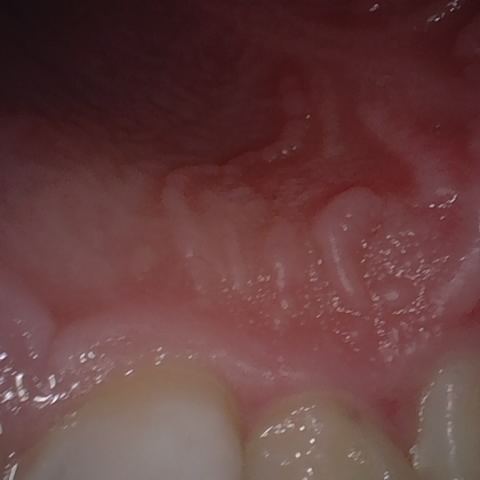

NHD39990

Annotated as "Good"